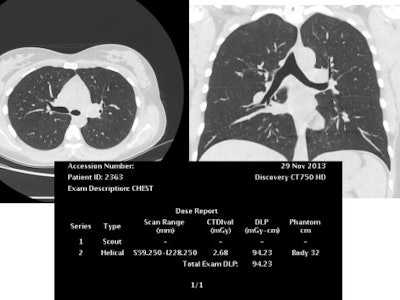

This reconstructed noncontrast CT image of the chest (lungs) was also achieved with reduced tube voltage of 80 kVp and automatic tube current modulation.A great enthusiast for iterative image reconstruction, he believes such techniques spell change for overall radiation reduction to patients and the wider population. However, he is aware that even when such tools are available, some doctors continue to choose standard protocols on advanced CT machines when low-dose protocols would be feasible.